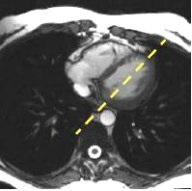

On a sagittal localizer, prescribe and acquire a series of axial locations that cover the heart anatomy of interest using an ungated 2D FIESTA sequence.

On an axial that displays the mitral valve, prescribe and acquire a long axis 2-chamber view using an ungated 2D FIESTA sequence.

Figure 3. Long axis 2-chamber viewFigure 4. 4-chamber view